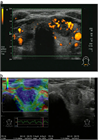

1. 超音波で悪性を疑う所見としては、縦横比>1(感度40.0%、特異度91.4%)、境界部棘状(感度48.3%、特異度91.8%)、著明な低エコー(感度41.4%、特異度92.2%)、微細石灰化(感度44.2%、特異度90.8%)、粗大石灰化(感度9.7%、特異度96.1%)であった(推奨度2)